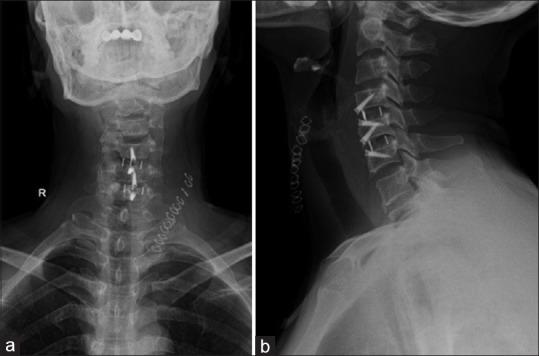

Cervical osteophytes may be seen in diffuse idiopathic skeletal hyperostosis, ankylosing spondylitis, posttraumatic, postoperative, degenerative causes, cervical spondylosis, and infectious spondylitis. A cervical osteophyte is very rarely considered among the differentials for symptoms of dysphagia. C5-C6 as well as C6-C7 being a site of greater load-bearing and mobility, the propensity to form osteophytes is high, with a small osteophyte leading to local mass effect. A 42-year-old male patient presented with mild dyspnea and significant dysphagia since 8 months, accompanied by dysphonia, weight loss, and intermittent aspiration. Clinical examination including neurological examination was normal. A barium swallow showed that osteophytes were severely protruding and displacing the lower pharynx and the proximal esophagus anterosuperiorly. The patient underwent surgical removal of the osteophyte through Smith-Robinson approach. Complaints of dysphagia were significantly decreased in postoperative period. A thorough evaluation is necessary to rule out other causes of dysphagia. Surgical management of this uncommon condition might be considered after confirmation of the osteophyte to be the offending lesion as it has favorable clinical outcomes.

颈椎骨赘可见于弥漫性特发性骨肥厚、强直性脊柱炎、创伤后、术后、退行性病因、颈椎病和感染性脊柱炎。在吞咽困难症状的鉴别诊断中,颈椎骨赘很少被考虑。C5-C6以及C6-C7是负重和活动度较大的部位,形成骨赘的倾向较高,小的骨赘会导致局部肿块效应。一名42岁男性患者自8个月以来出现轻度呼吸困难和明显的吞咽困难,伴有声音嘶哑、体重减轻和间歇性误吸。包括神经系统检查在内的临床检查均正常。吞钡检查显示骨赘严重突出并将下咽和食管近端向前上方推移。患者通过Smith-Robinson入路接受了骨赘切除术。术后吞咽困难的主诉明显减轻。有必要进行全面评估以排除吞咽困难的其他原因。在确认骨赘为致病病变后,可考虑对这种罕见情况进行手术治疗,因为其临床效果良好。